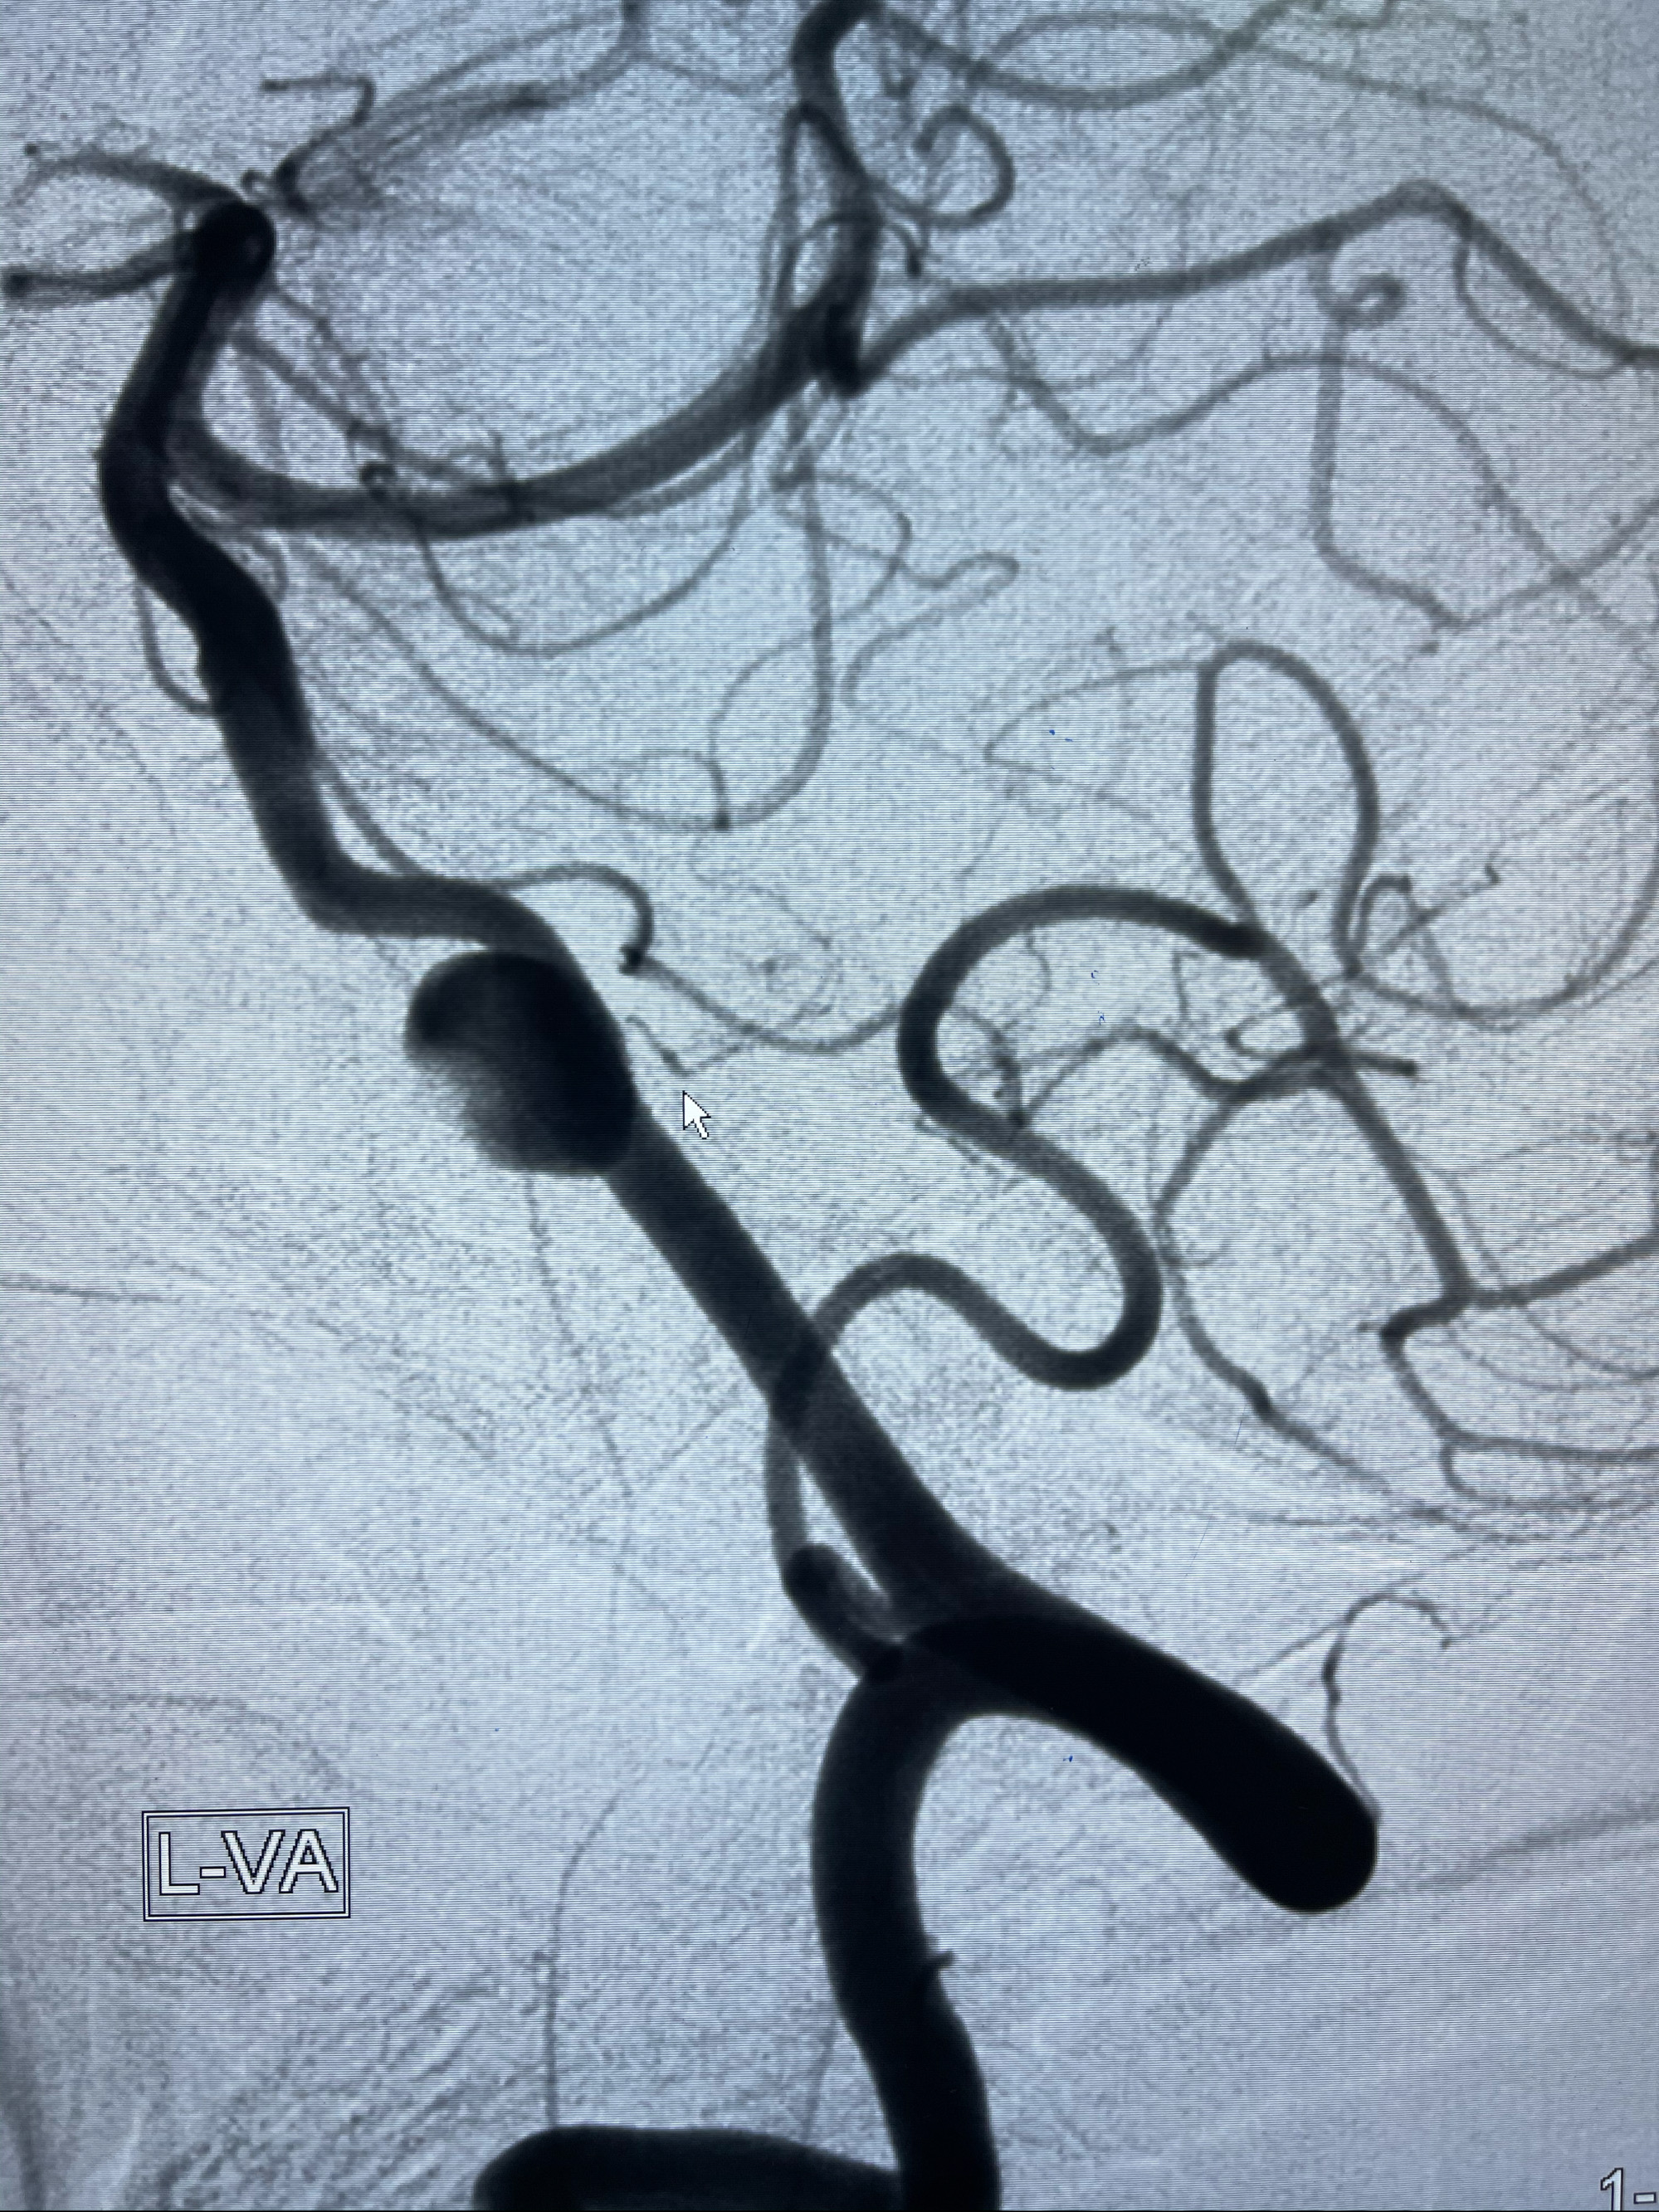

2021-03-08行全脑血管造影

左侧椎动脉V4夹层动脉瘤多支架辅助栓塞:

工作角度造影